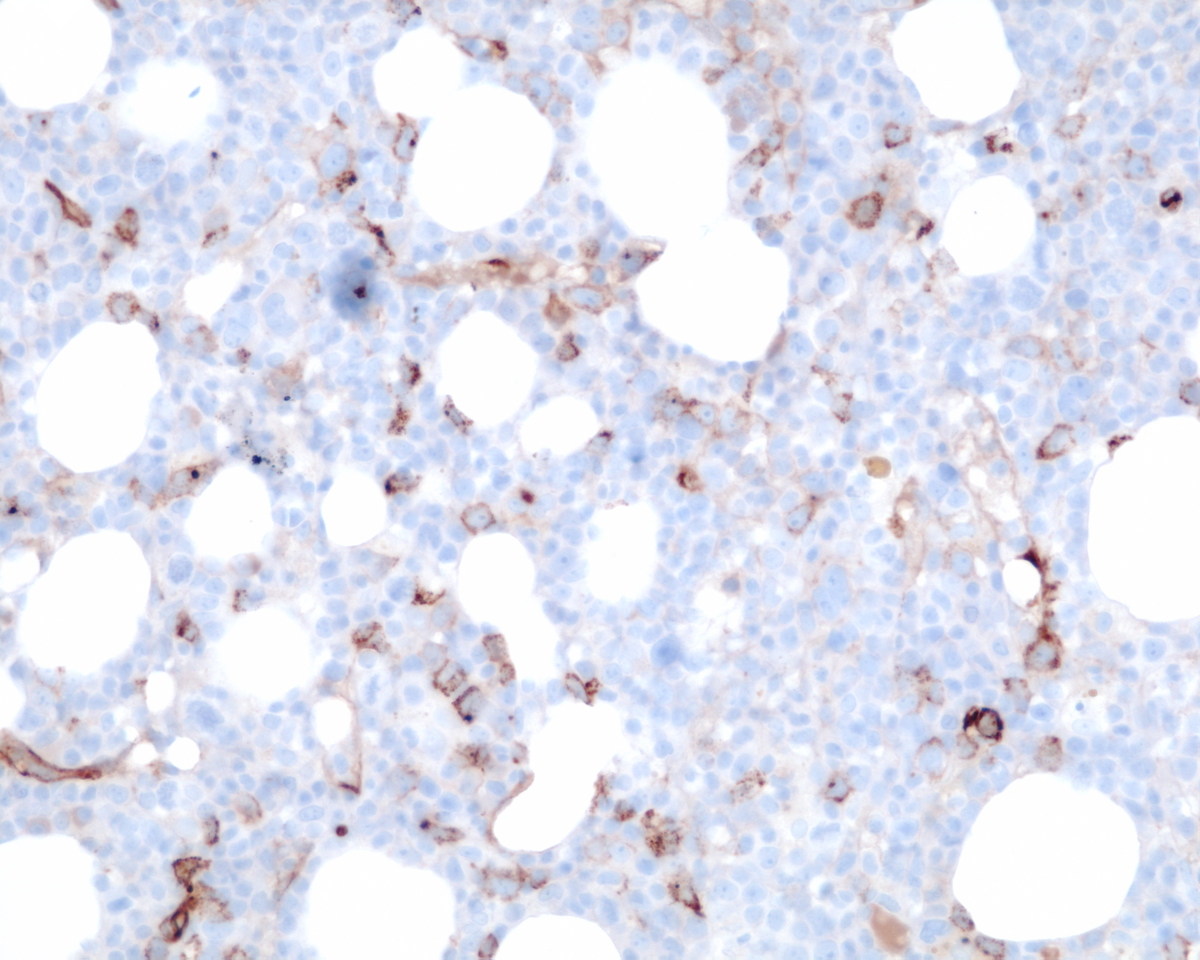

Immunohistochemical stains showed marked increase of megakaryocytes, including numerous small, monolobated forms, which are strongly positive for CD61. CD34 and CD117 highlight increased immature cells, approximately 10% of the nucleated marrow elements. Reticulin shows mild diffuse increase in fiber deposition. An iron stain shows adequate stainable iron. Immunophenotyping by flow cytometry reveals approximately 7% of the total gated events in the dim CD45 positive gate, which coexpress CD34, CD117 and myeloid antigens. A subset of the cells coexpress CD41 and CD61 indicating megakaryocytic lineage.

| Immunohistochemistry CD34 | ![]() |

| Immunohistochemistry CD117 | ![]() |